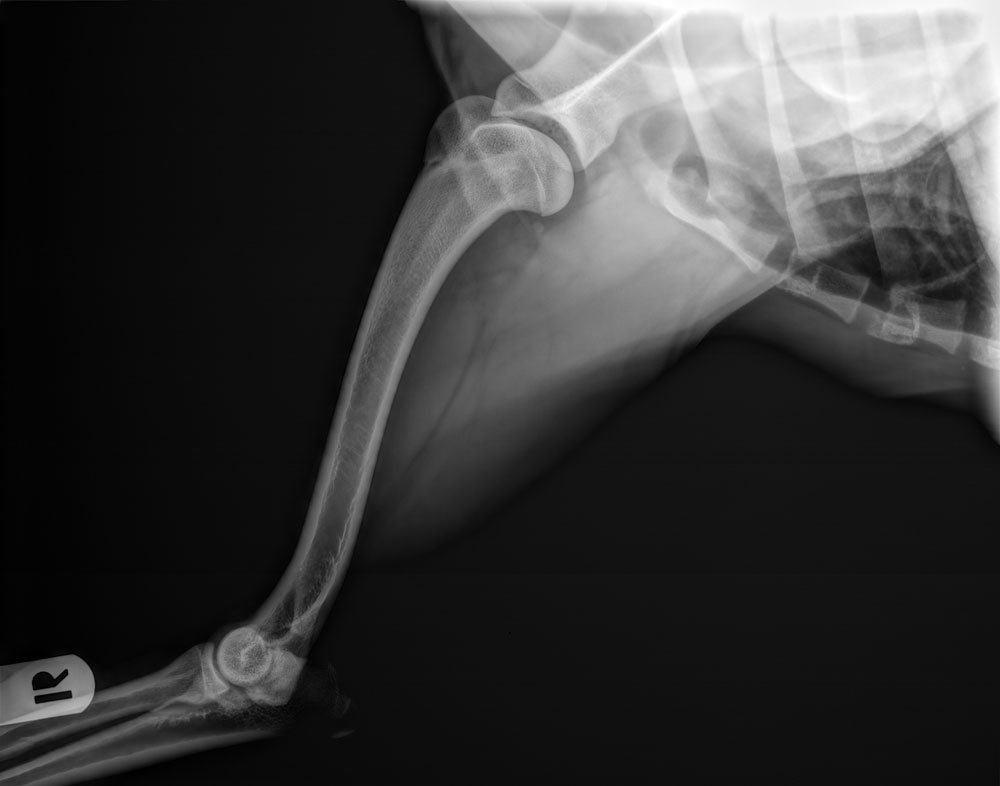

| Schouders : | normaal (foto's: links, rechts, verklaring dierenarts) | |